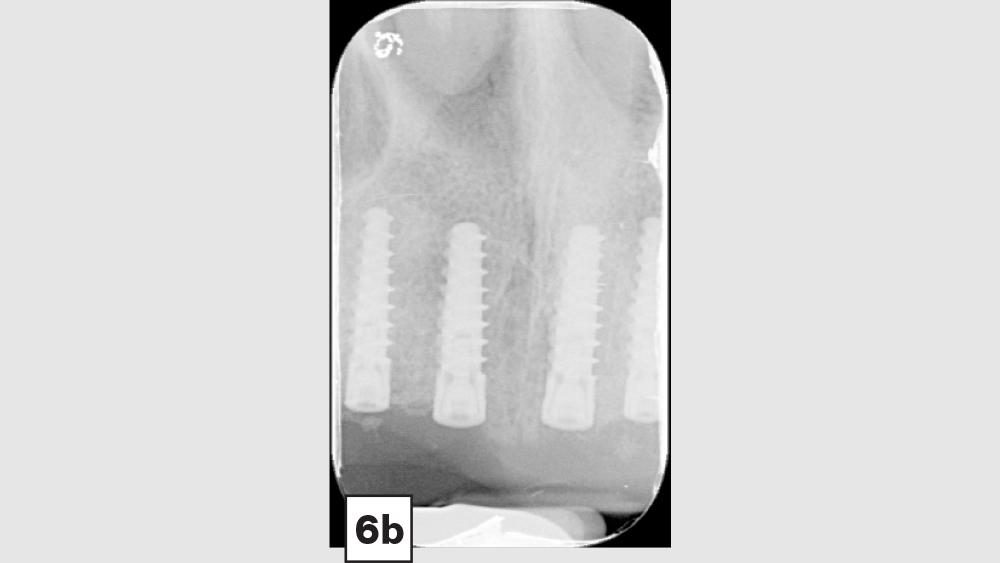

Digital treatment planning (DTP) with the team at Glidewell Laboratories allows me to ensure that implants are precisely placed, with full consideration given to the desired esthetics of the final restorations. But there was another unique element involved in planning the case described below: While it was esthetics that caused the patient to seek treatment, his career as a glass blower required his implants to be placed in functionally ideal positions. The potential complexity of these multiple requirements solidifed my decision to approach his case with implant positioning predetermined via DTP.

This patient came to me with four missing anterior teeth in positions #7–10. He had been missing these teeth for some time and was wearing a temporary denture to address the cosmetic issue this created. When he came to my practice, he was in a financial position to solve the problem permanently with implant restorations. Based upon the anterior space available and the fact that the patient’s surrounding tissue was in good health, I chose to move forward with Hahn™ Tapered Implants and BruxZir® Esthetic restorations.